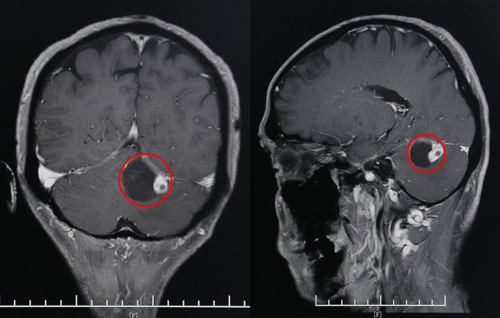

CT影像显示,患者左侧小脑囊实性占位(红圈部分)

在家人的一再劝导下,黄先生还是决定去医院走一趟。这不查不知道,一查吓一跳——在当地的县人民医院,头颅CT显示,黄先生的左侧小脑半球占位。

经过进一步检查后,黄先生左侧小脑半球囊实性占位,考虑血管母细胞瘤可能大。院神经外科专家团队经过讨论后认为,患者有手术指征,考虑在全麻下行枕下入路小脑肿瘤切除术。但由于肿瘤位置较高,贴近小脑幕,手术风险较高。